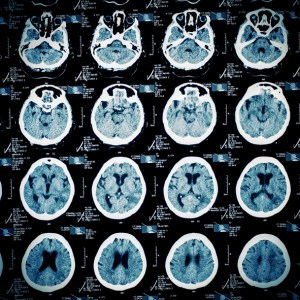

Photophobia and Traumatic Brain InjuryA report by Optometry Review published in December 2015 explored common vision problems, especially photophobia, that occur after a traumatic brain injury. The report was prepared by Christopher L. Shur, OD, and several other eye doctors. To determine the severity of at TBI (mild to severe), doctors usually use a Glasgow coma scale. According to the report, 75% of people who experience TBI have a mild TBI, also commonly called a concussion. Signs of a TBI include vision difficulties, headaches, a visible wound, confusion, cognitive impairments, loss of muscle function, memory loss, and headaches